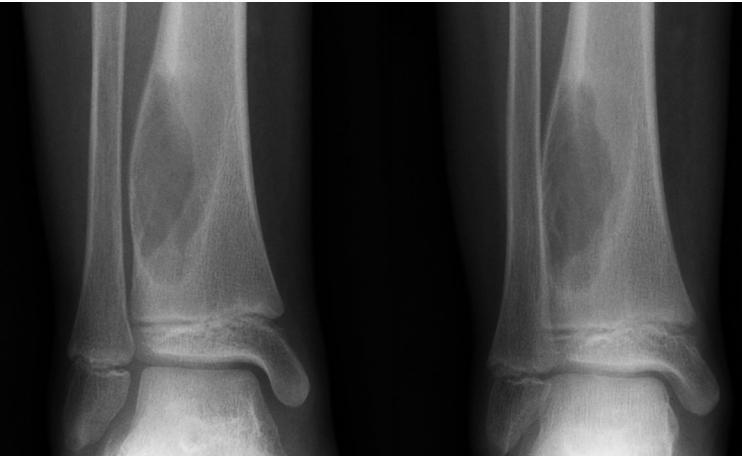

Aneurysmal Bone Cyst

- Child - young adult

- Metaphysis of long bone

- X-ray:

- Well-defined cyst

- Trabeculated

- Eccentrically placed

- Ballooning

- Bloody content

- Treatment:

- Curettage and bone graft

- Metaphysis, Eccentric